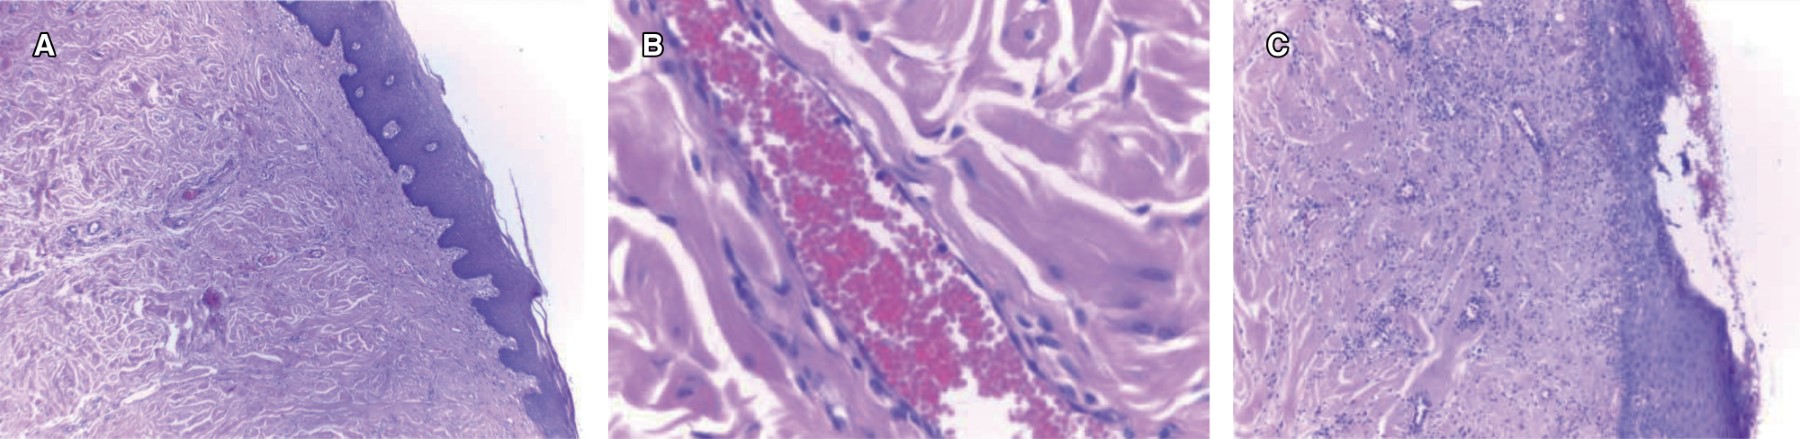

Se programa biopsia incisional bajo anestesia local, obteniendo muestra de 1.5 × 1 × 0.5 cm color blanquecino, aspecto fibroso y consistencia ahulada, la cual se envía a estudio histopatológico (Figura 2). El resultado indica que es compatible con fibroma irritativo.

La literatura refiere que el rango de edad en el que puede presentarse este tipo de lesión va de los nueve hasta más de 90 años.10 Histopatológicamente, el fibroma se presenta recubierto por una capa de epitelio escamoso estratificado delgado, acompañado de una atrofia de las crestas epiteliales debido a la masa fibrosa subyacente. Sin embargo, la superficie puede presentar hiperqueratosis debido a la fricción crónica de baja intensidad o mostrar focos de ulceración cuando el trauma es intenso. Este epitelio recubre una masa nodular de tejido conjuntivo fibroso denso formado por abundante colágeno maduro bien organizado, con predominio del tipo I y III, similar al de las cicatrices, aunque en algunos casos es de naturaleza laxa. Los haces de colágeno pueden estar dispuestos en forma radial o arremolinada, encontrándose entrelazados y mezclados con diversos fibroblastos, fibrocitos y pequeños vasos sanguíneos, pero generalmente se encuentran bien localizados. La lesión no se presenta encapsulada y se encuentra más a menudo por debajo de la superficie epitelial. Por lo general esta inflamación es crónica y se compone principalmente de linfocitos y células plasmáticas.11